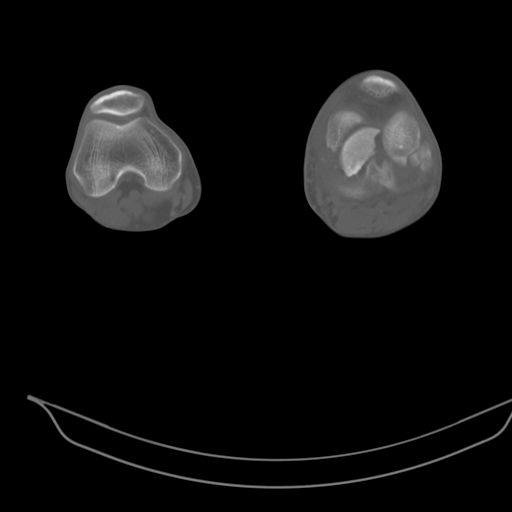

застарелый многооскольчатый перелом мыщелков бедра |

В клинику поступил больной 34 лет с закрытым многооскольчатым внутрисуставным переломом мыщелков левой бедренной кости со смещением.

Травма в шахте, 4 недели назад. Лечился в местной ЦРБ в гипсовой повязке. В области сустава была ссадина, которая на данный момент полностью зажила.

Сейчас в суставе сгибательная установка под углом 130*. Движения резко ограничены, болезнены. Больной направлен к нам для решения вопроса об эндопротезировании коленного сустава, однако мы не видим альтернативы артродезу.

Есть ли на ваш взгляд шанс избежать замыкания сустава у этого молодого и физически активного пациента?